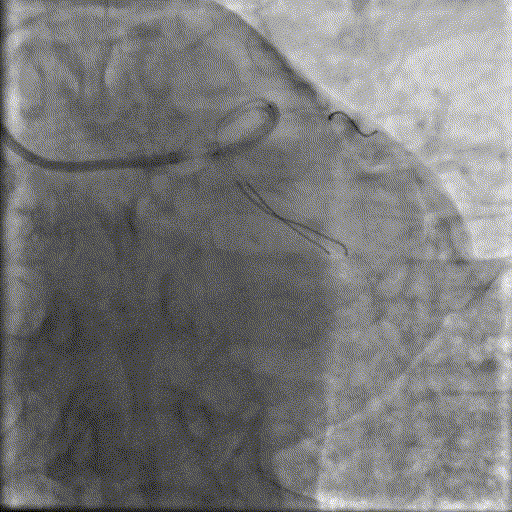

球囊预扩

用预扩球囊扩张LAD病变,支架无法通过。为了解血管病变分布情况及钙化程度,遂启用IVUS检查。

术前腔内影像学IVUS指导

IVUS提示LAD近中段钙化病变,中段可见360°环形钙化。

冲击波球囊治疗

3.0x12@4atm 冠脉血管内冲击波导管顺利推送至前降支近端,但无法通过成角钙化处,故于血管近端就地进行10个周期治疗,复查造影见近端狭窄明显减轻;再次选择2.5x12@4atm冠脉血管内冲击波导管推送至成角钙化处,逐步掘进扩张病变并给予冲击波治疗,最终顺利通过成角钙化处,并于前降支中段再次进行10个周期的冲击波治疗。

支架植入并后扩

于LAD近中段串联植入两枚药物洗脱支架,经非顺应性球囊后扩张支架,复查造影及IVUS提示支架膨胀完全,贴壁良好,无夹层撕裂。